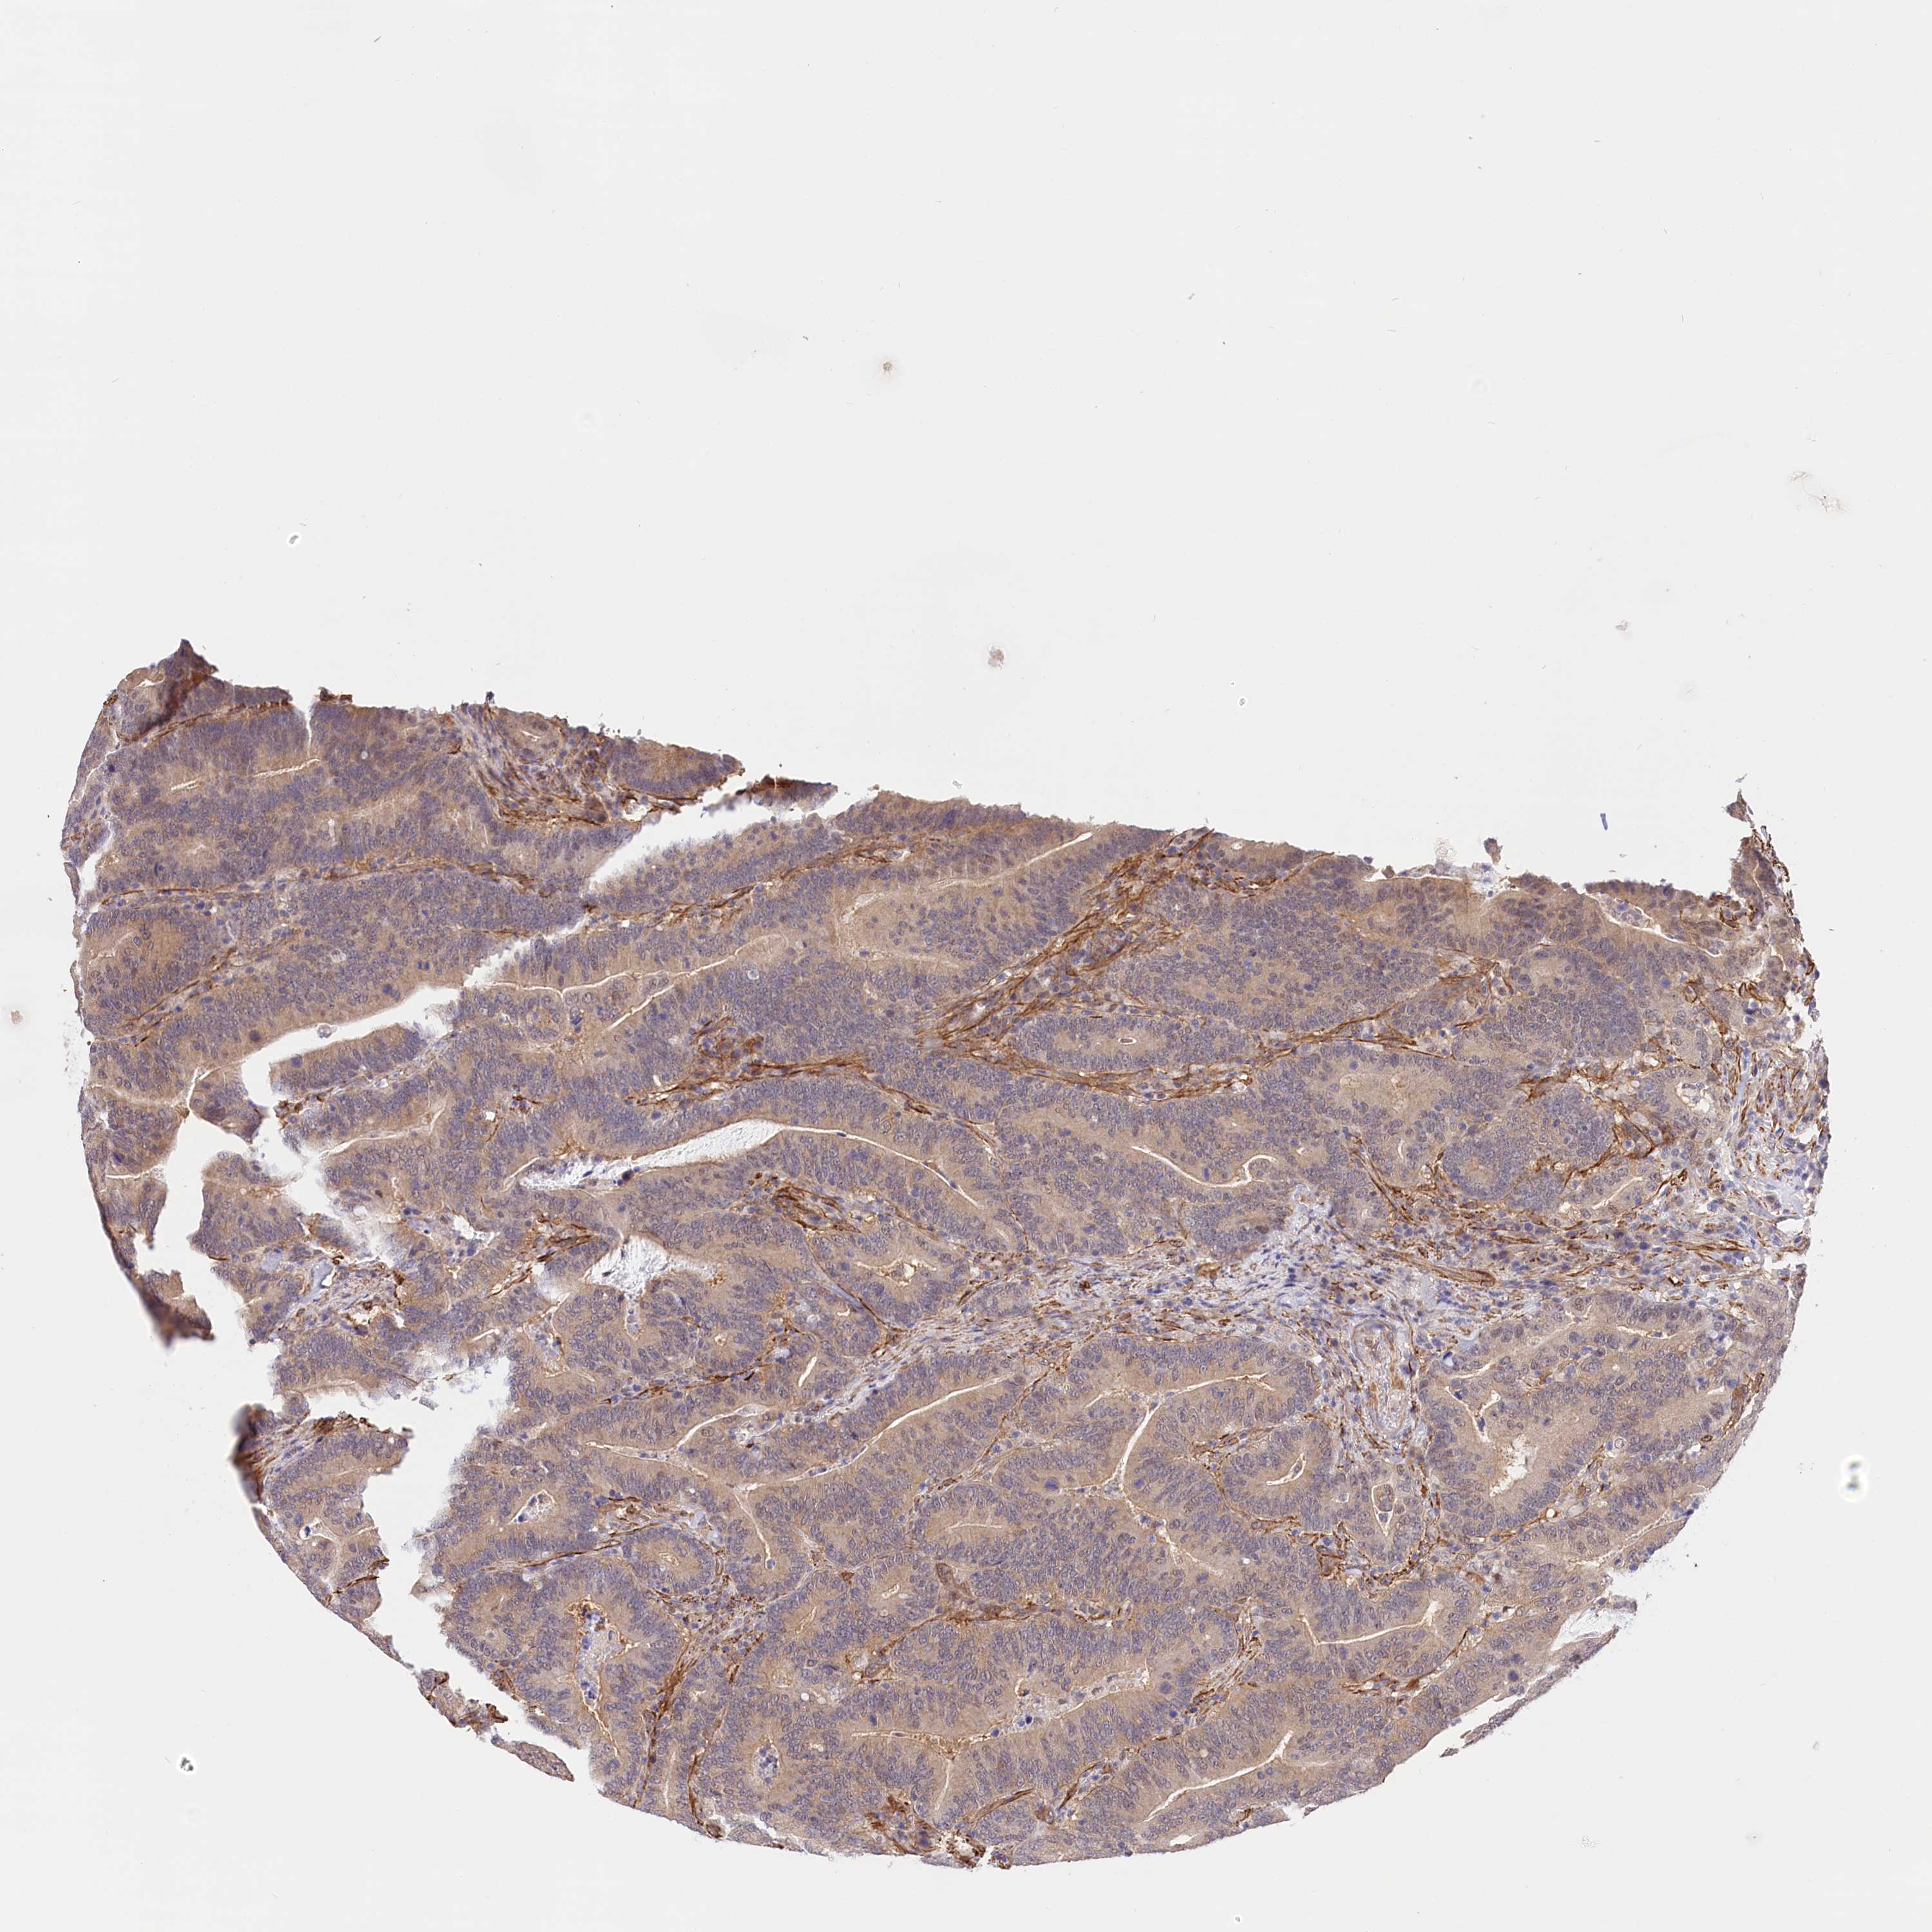

Colorectal cancer

Colon adenocarcinoma

Average pTPM 11.3

Number of samples 254